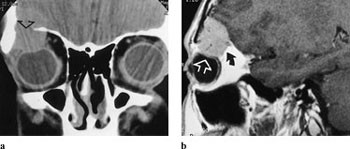

CT viser homogen fortykkelse av synsnerven både i aksial- og koronalplan. Hvis CT benyttes, hører koronale snitt med, og man bør undersøke uten og med intravenøs kontrast. Selve nerven kan ikke sees som en separat struktur, ikke engang etter kontrast. Utvidelse av optikuskanalen er vanlig. MR viser enten fusiform, eksentrisk eller tubulær fortykkelse (fig 5a). T1-vekting viser lik intensitet mellom tumor og nerven, mens T2-vekting viser økt signal. Kontrastopptaket er ofte beskjedent. Ved intrakranial utbredelse sees fortykkelse av chiasma, med lav signalintensitet på T1- og økt signal intensitet på T2-bilder (fig 5b). Fettsuppresjonsteknikk er nødvendig for å skille kontrastoppladning i tumor fra høyt signal i orbitalt fett.

CT viser diffus fortykkelse av synsnerven, med kraftig kontrastopptak i tumor. Forkalkninger styrker differensialdiagnosen. Det er vanskelig å påvise kalk ved MR, og derfor er begge metodene til nytte. Ved MR har svulsten lavere intensitet enn selve synsnerven (fig 6 a). Små meningiomer kan som regel påvises bare ved bruk av gadoliniumkontrast, og gir kraftig kontrastoppladning (fig 6 b). Denne metoden fremstiller også best eventuell intrakranial utbredelse av tumoren (7). Den beinete optikuskanalen kan være utvidet. Ordinære skjelettbilder av foramen optici er i dag oftest erstattet av tynne CT-snitt i to plan.